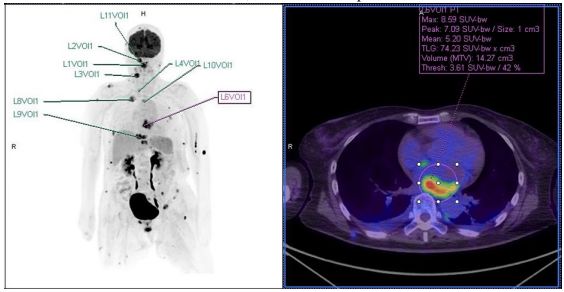

96. 一位 65 歲女性,無腫瘤病史,發現全身多處腫塊,whole body PET (下圖) 及 MRI 顯示軟組織、骨、腦、肺有多個 1-2 cm 之腫瘤,PET 另外發現左心房內有 約 4.5 cm 區域之高代謝性疑似病灶。頸部、上顎、脊椎三處腫瘤之組織切片,病 理檢驗皆顯示為 spindle cell neoplasm with moderate pleomorphism and increased mitoses,分化方向不明確,FISH 則發現 MDM2 amplification。

關於這些腫瘤,下列描述何者最可能是正確的? (A)依部位相關發生率來說,此腫瘤最有可能是 angiosarcoma (B)FNCLCC grade 是已知的最重要預後因子 (C)常見的 copy number 異常包括 PDGFRA & EGFR gain 及 CDKN2A loss (D)TP53 missense mutation 是最常見的基因變異